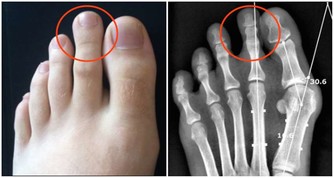

*****1.鈣*****

隨著年齡的增長,您可能會失去更多的這種礦物質而無法吸收。這會使您的骨骼更容易骨折(骨質疏鬆症),尤其是對於更年期後的女性。鈣有助於您的肌肉,神經,細胞和血管正常工作。您大部分是從骨頭中獲取的,而骨頭是從食物中獲取的。50歲以上的女性和70歲以上的男性應比其他成年人需要的更多。牛奶,酸奶和奶酪是很好的來源。